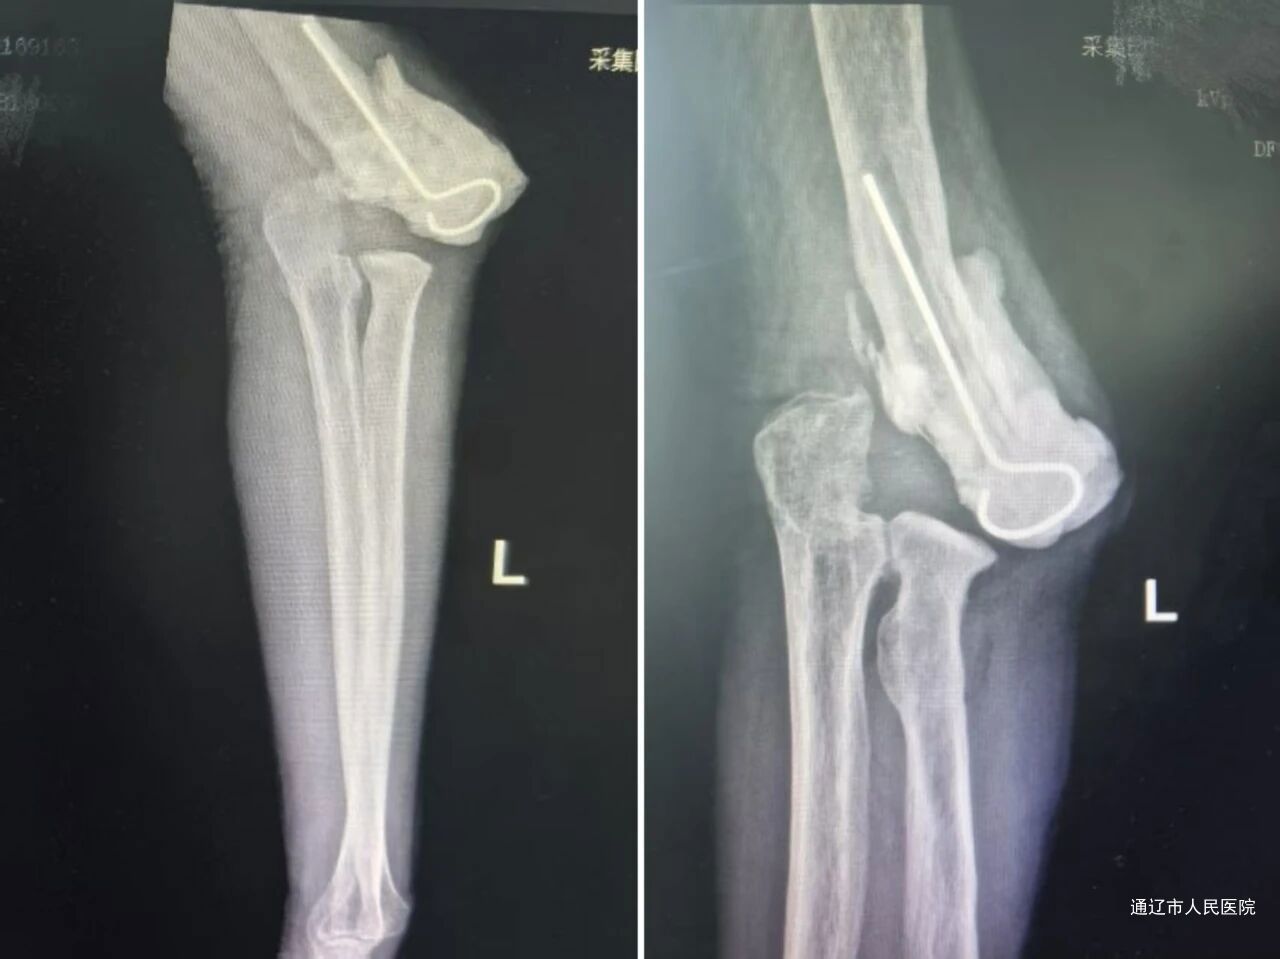

术后X线